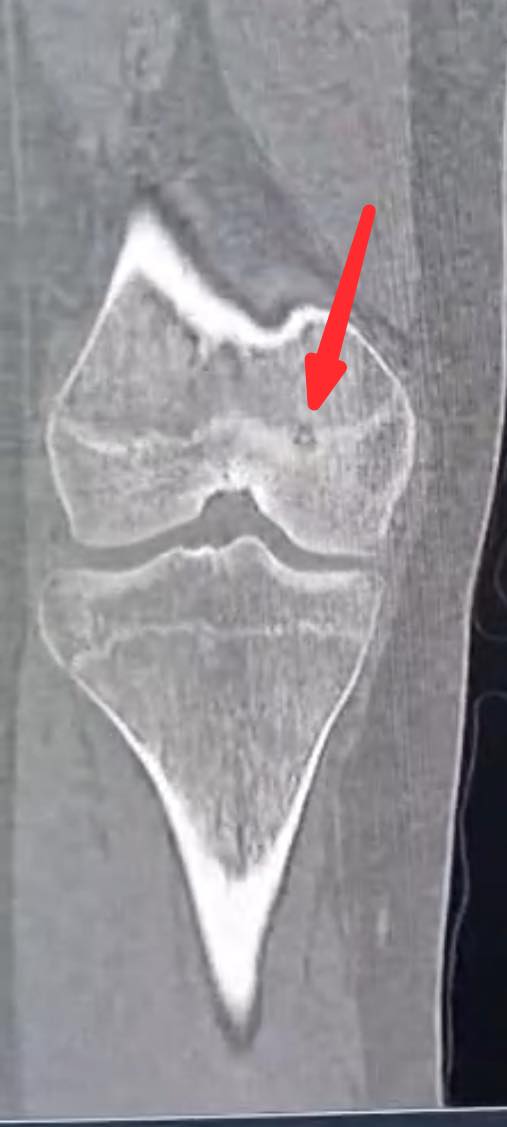

السوسنة - اجرى الكادر الطبي في مستشفى الأميرة بسمة عملية نوعية دقيقة لعلاج ورم عظمي حميد من نوع (Osteoid Osteoma) باستخدام تقنية الكي بالتردد الحراري (Radiofrequency Ablation) الموجهة بالأشعة المقطعية.

وبين الفريق الطبي أن خصوصية هذه الحالة تكمن في عمر المريضة (14 عاماً) حيث استقر الورم مباشرة على صفيحة النمو (Growth Plate) في عظم الفخذ البعيد. وتعتبر هذه المنطقة من الحساسية بمكان إذ ان أي خطأ قد يؤثر على النمو المستقبلي للعظم ما جعل استخدام تقنية الكي الحراري تحديا كبيرا يتطلب دقة فائقة لتجنب إلحاق أي ضرر حراري بالأنسجة المحيطة.